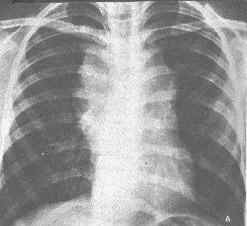

2)x線檢查,下肢的淋巴管造影,對確定腹膜後淋巴結受侵有一定價值。對其他可疑的部位作x線攝片和造影檢查亦很有診斷價值。

3)CT檢查,對縱隔、肺、肝、脾、腹部、腹膜後、盆腔等部位的占位病變,有很高的診斷價值。